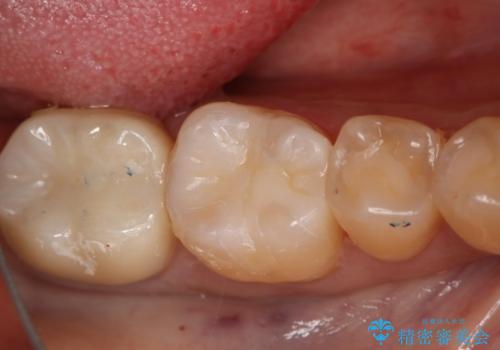

- 過去に他院で治療した部位が材料劣化を起こしていたため、セラミック治療を希望された患者様です。

切削量を考慮し、セラミックインレーを選択しました。

虫歯が深かったので、CRを詰めた上で形態を整えています。